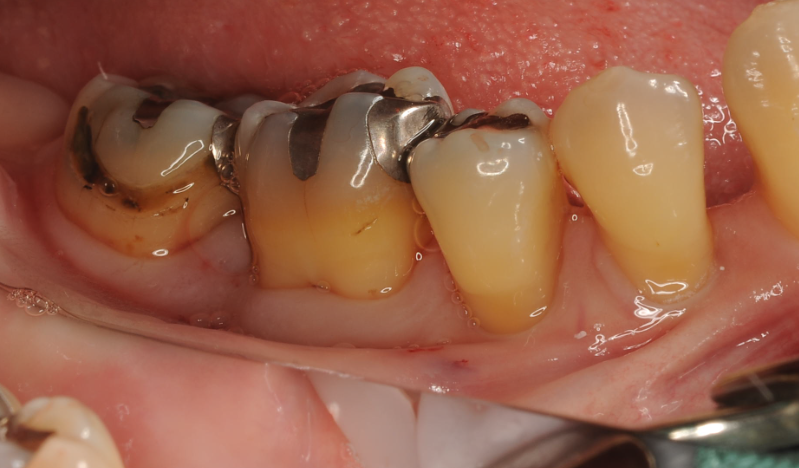

EPPTテクニックを使い歯間乳頭を一切切らずにマイクロサージェリーを行っております。

再生が見られ、ポケットが安定致しました!!